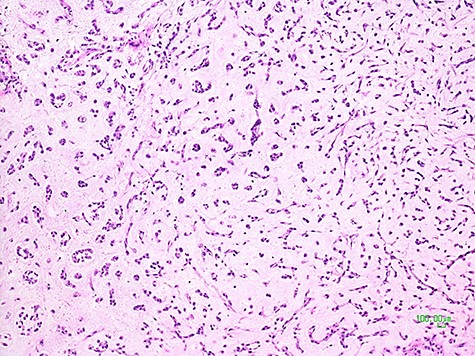

Being this sarcoma localized in two different sites, pelvic-retroperitoneal and gluteal, the operation was carried on in two surgical steps. After median laparotomy, in the left pelvic region, a mass of about 10 centimeters of maximum diameter, dislocating the bladder anteriorly, the left iliac vessels cranially and medially the sigma, was documented. Dissection and isolation of the mass from the surrounding structures were completed. A specimen of the mass capsule and myxoid material resulted to be a malignant mesenchymal neoplasia with a myxoid appearance. The mass was removed with radical intent. After its complete clearance, the entire surgical field was treated with argon-laser electrofulguration and, immediately after, with a peritoneal extensive lavage (according to Kuramoto technique) [10]. At the end of this surgical procedure, the operation was considered R0. Therefore, the patient was placed on the right flank position. An incision of the left buttock region was made, and, Deeping within the muscle planes, a lobulated mass of about 8 centimeters in diameter was found. After its complete removal, an argon-laser electrofulguration of the entire surgical area was applied. Two different surgical specimens were analyzed by the histopathological laboratory, labeled retroperitoneal-pelvic and left buttock (gluteal) tumors. At the gross examination, they both presented multiple fragments of glistening and gelatinous tissues with intratumoral hemorrhage, weighting 190 and 144 grams, respectively. Their histological features were comparable and characterized by multiple lobules with abundant myxoid-chondromyxoid matrix in which monomorphic cells with uniform nuclei and eosinophilic cytoplasm connected one another to form cords, small clusters, and complex trabecular or cribriform structures. No mitotic activity was seen; diffuse areas of hemorrhage and necrosis were identified (Fig. 3).

Histological picture of the tumor showing clusters and chords of medium-sized epithelioid cells immersed in a myxoid matrix (H&E, ×100).